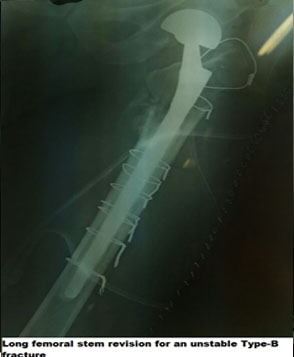

VANCOUVER TYPE B

A 66-year-old male sustained an injury after a trivial fall presented with an unstable fracture and inability to bear weight. Revision performed with a long stem, and immediate mobilization was possible.